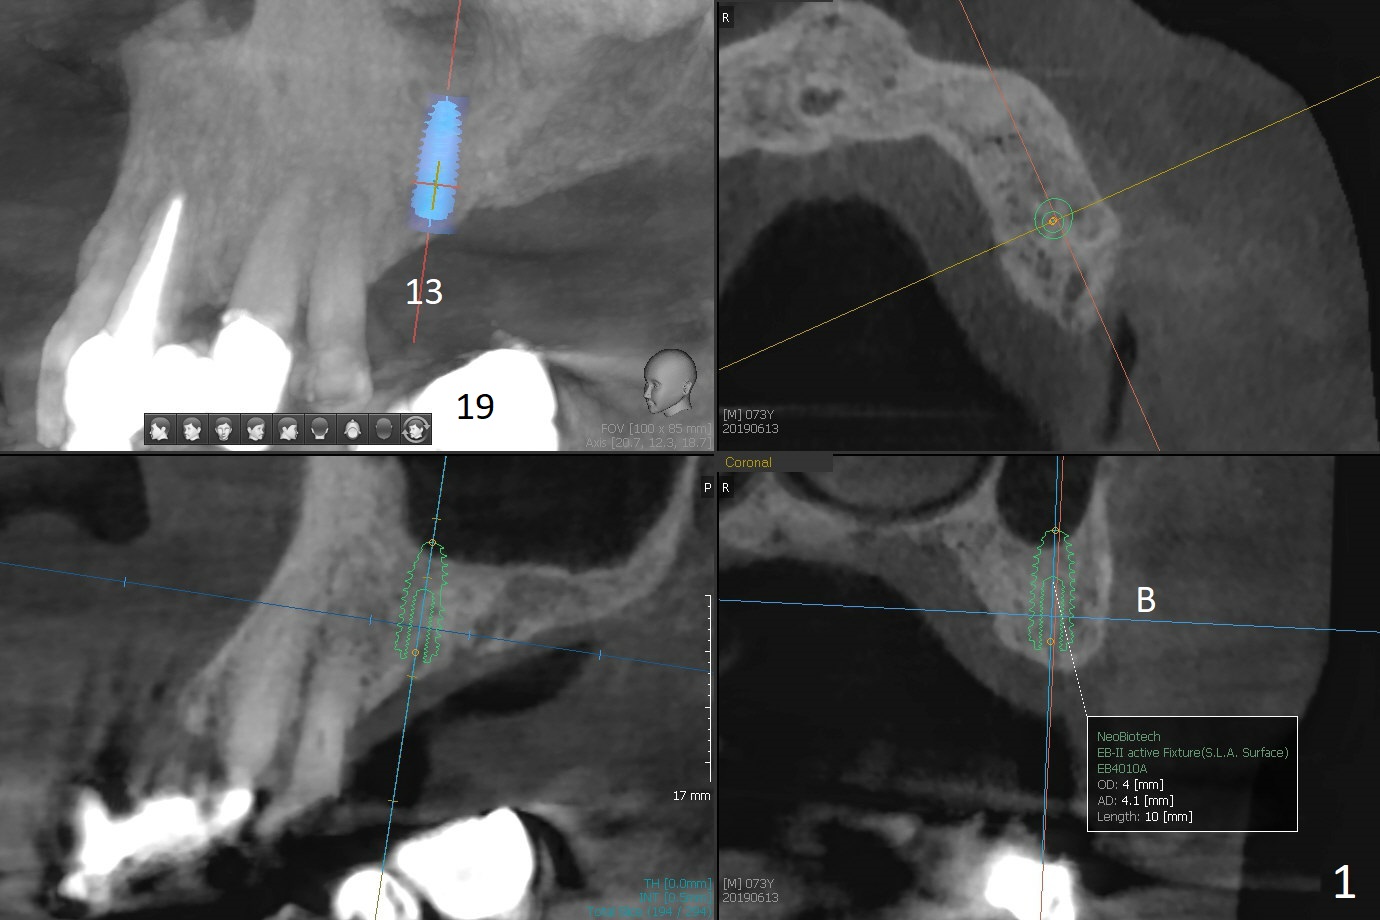

A 73-year-old man returns for #13 and 14 implants (guide) following #19 and 29-31 ones (Fig.1,2). Sinus lift (Fig.2 red circle) will be also assisted with guide and PRF at #14 (yellow curved line (Metronidazole)).